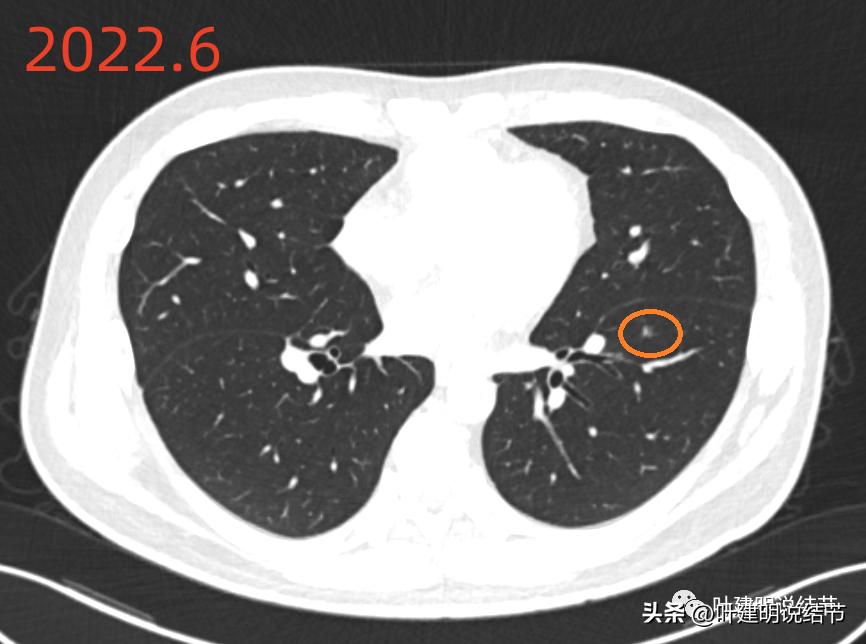

2022年6月的影像:

左下叶病次病灶(以下称病灶A)是微小磨玻璃结节,密度略不均,显得像混合磨玻璃密度,但纵隔窗应该未见明显实性成分的,整体轮廓较清,膨胀性不明显。感觉像慢性炎伴不典型增生或肺泡上皮增生可能性大。

先看2022年6月的片子时,感觉左下叶红色圈起来的像原位癌,桔色圈起来的像不典型增生可能性大些。但回顾2019年的片子,当时有肺炎,如绿色圈起来的范围内都是炎症性的,那时候这两个病灶也有,但红色这处当时瘤肺边界模糊点,桔色这处密度比现在感觉要高点,又结合当时炎症过,所以总体看来,桔色的考虑慢性炎性结节可能性大;红色的虽不能除外原位癌,但也无法除外炎性,至少风险应该不算高,如果再随访下也可以的。若手术,红色的要后基底段切除,桔色的要前内基底段切除,就留下外基底段与背段感觉有些孤立;若均楔形切除也是可以的,但若均是炎性,则不划算,我个人意思仍是风险不大情况下,再观察下,反正危险不大嘛!